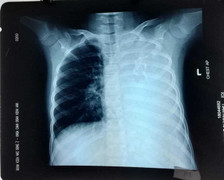

5 tiếng căng thẳng cứu người đàn ông có khối u gần 3kg chèn ép tim phổi

Dù có khối u với đường kính 20cm, nặng gần 3kg trong lồng ngực nhưng người đàn ông không hề hay biết.

U trung thất có rất nhiều biểu hiện lâm sàng, các biểu hiện lâm sàng thường phụ thuộc vào vị trí u trung thất và tình trạng chèn ép, xâm lấn các thành phần trong trung thất.